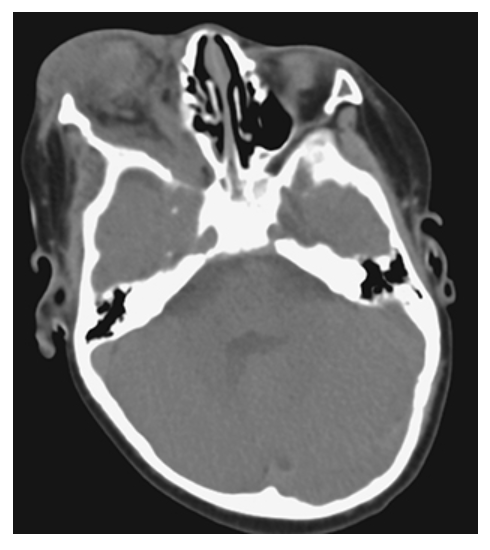

Neurofibromatosis (NF1). Axial NECT shows a soft tissue density infiltrative mass of the right orbit with moderate exophthalmos.